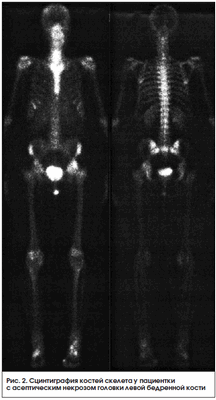

Сцинтиграфия активно используется в оценке состояния перфузионно-метаболических процессов при заболеваниях опорно-двигательного аппарата у детей. Так, по данным отечественных авторов, она выходит на 1-е место и составляет до 1/3 всех радионуклидных исследований, за рубежом эта цифра достигает 60% [29]. Остеосцинтиграфия обладает высокой чувствительностью к любым патологическим изменениям в кости. Недостатком этого метода является низкая специфичность из-за тропности РФП в участках скелета с высоким остеогенезом, однако диагностическую ценность метода можно повысить с помощью полифазной остеосцинтиграфии, позволяющей оценить не только костный, но и мягкотканный компонент. Особенно этот метод информативен при диагностике дистрофических поражений скелета, в т. ч. болезни Легга - Кальве - Пертеса, которая встречается только у детей и подростков и составляет 25-30% среди заболеваний тазобедренного сустава. Ранняя диагностика состояния кровообращения в области пораженного тазобедренного сустава необходима для выбора консервативного лечения и влияет на прогноз заболевания. Также этот метод информативен при аваскулярном некрозе взрослых, особенно у пациентов с длительным болевым синдромом при отрицательной рентгенологической картине (рис. 2).